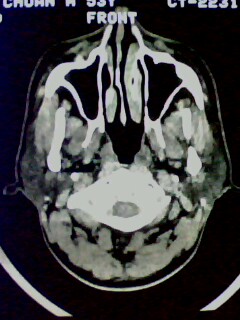

以下是引用随光逐影在2009-5-20 19:22:00的发言:[br]1)考虑左上颌骨近中线区含牙囊肿。2)鼻中隔右突偏曲。3)双侧下鼻甲肥大。